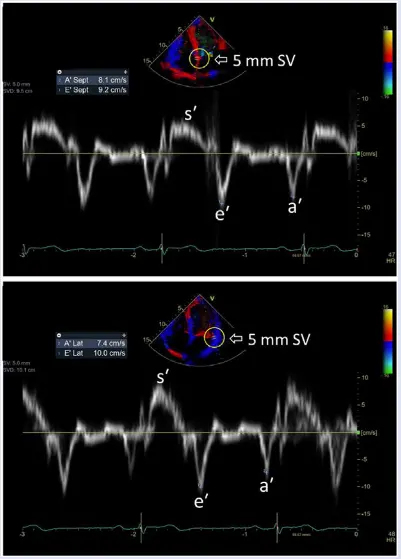

Mitral annular velocity: e’ velocity (cm/s): peak early diastolic modal velocity after ECG T-wave

Mitral annular velocity: a’ velocity (cm/s): peak late diastolic modal velocity after ECG P-wave

As a general rule of thumb, normal LV relaxation is suggested by medial e’ ≥ 9 cm/s and lateral e’ ≥ 12 cm/s. However, values can vary by age 👇

- According to Dr. Oh, e’ velocity is money 💵 because normal LV relaxation (e’) means you must have normal diastolic function. This is reflected in the Step 1→Step 2 algorithm (Figure 2) proposed in the 2025 guideline update.4

- In other words, you can stop looking for other markers of diastolic dysfunction if you have normal e’ velocities.

- “Once you see that e’ is normal, you don’t need to look at anything else because you cannot have diastolic dysfunction with normal e’ velocities” - Dr. Oh

- “Normal e′ velocity is unusual in patients with diastolic dysfunction related to a myocardial abnormality or disease, which is a main reason that the joint Diastology Working Group recommends that an evaluation of diastolic function begins with e′ in patients with normal LV ejection fraction.” 3

- In healthy hearts, a significant amount of LV ejection and LA filling results from descent of the mitral annulus toward the apex. This longitudinal motion normally precedes filling.1

- A bunch of comorbidities (e.g., HTN, obesity, diabetes) can lead to impaired myocardial relaxation and restoration forces, and ↑ lengthening load (LA pressure) → reduced and delayed longitudinal motion and e′ velocity

Mitral inflow pattern in a ~30 yo patient with severe LVH who initially presented with HTN emergency.

If you just base it off the patient having medial e’ >6, lateral e’ >7, or average >6.5, then you may conclude that she has normal diastolic function. However, I’d argue that this would be incorrect. The patient is a ~30 yo with severe LVH. Bearing in mind her young age, you should expect her e’ velocities to be much higher if she truly had normal diastology. With her very high E/A ratio, she has Grade 3 DD.